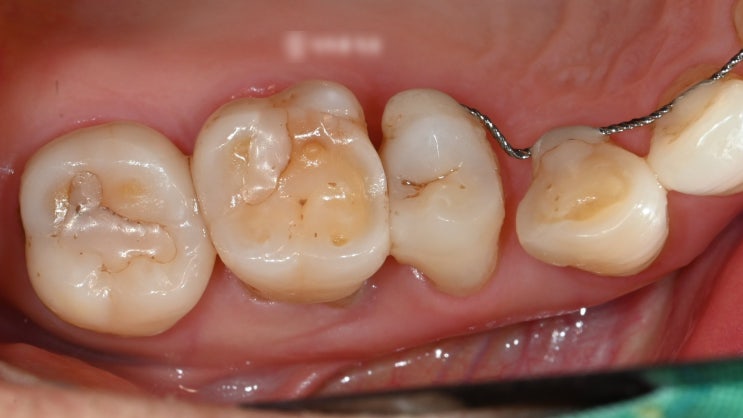

신촌역치과 정기검진의 중요성 다수의 충치 재발, 인레이, 신경치료

안녕하십니까, 대표원장 조민기입니다. 여러분들께서는 정기검진 을 받으신지 얼마나 되셨나요? 많은 분들...